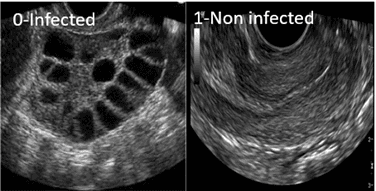

Abstract: Polycystic Ovary Syndrome (PCOS) is one of the most common causes of infertility for women around the world. It is a metabolic and hormonal condition that affects women of reproductive age. It is vital to detect this problem as soon as possible. Among all the possible diagnostic imaging ultrasound is the safest option as it has no risk of radiation. This research aims to create a system that will detect PCOS from ultrasound images. A dataset containing 3840 images of 2 classes which are infected and non-infected has been used in the research. Using techniques such as resizing, rescaling, center cropping the dataset has been preprocessed. A feed forward model using Convolutional Neural Network (CNN) architecture with 8 layers has been deployed for that task. The dataset was split into train, validation and test set. After training the CNN model with training data, the model has been trained further using adversarial training through Fast Gradient Sign Method (FGSM). Hyper parameter tuning was done for optimal result. The highest accuracy achieved by the model is 99.07% for epsilon=1.6 (adversarial training). The model’s output prediction has been explained by using Gradient Weighted Class Activation Mapping (Grad-CAM). After 1000 iterations, the 99% confidence interval for the model is [0.985,0.996].